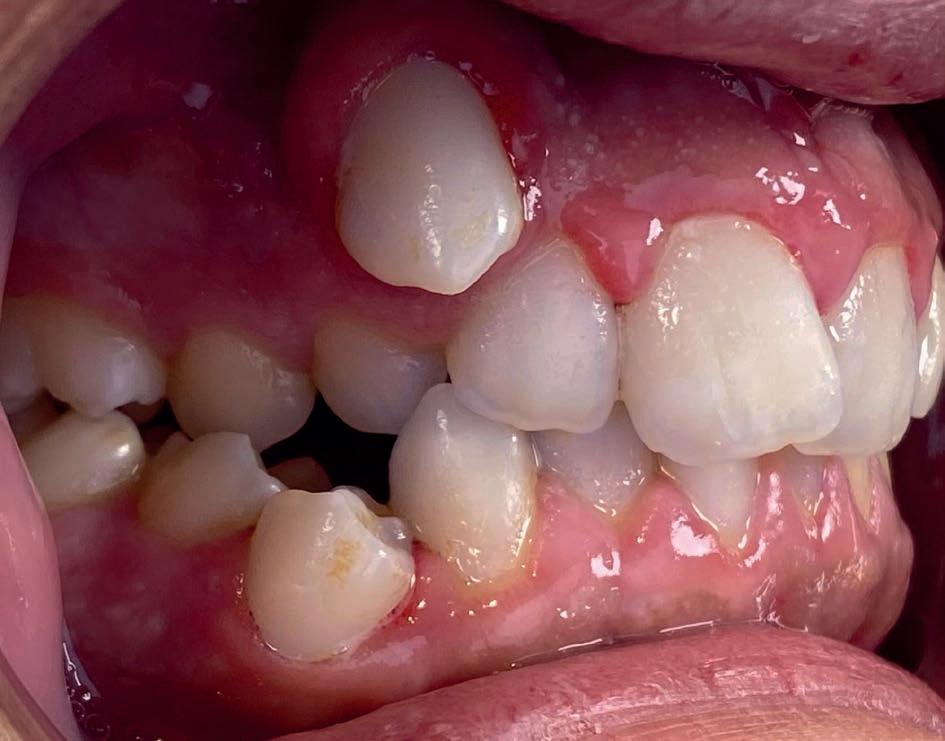

Casus in Proces

Patiënt Sonnie presenteerde zich met ernstig ruimtegebrek ter hoogte van de 13 en 44 en een kruisbeet aan de zijde van de 15 en 14. De 13 was ectostematisch gepositioneerd, waardoor extractie aanvankelijk als mogelijke behandeloptie werd overwogen.

Door een combinatie van verbreding en het inzetten van een D-gainer wordt de benodigde ruimte gecreeerd om alle elementen correct in de tandboog te positioneren, waardoor extracties kunnen worden vermeden. De behandeling zal binnen twee jaar worden afgerond; het eindresultaat wordt gedeeld in editie 2 van ons magazine.

Start behandeling

Midden behandeling

Laatste fase